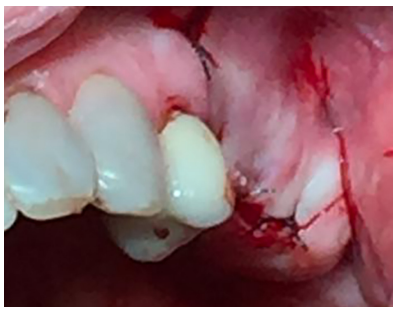

Se realizó una incisión lineal crestal con descarga distal para la obtención del campo quirúrgico. Se utilizó la técnica de fresado biológico a 100 rpm insertándose 3 implantes en posición 25, 26, 27 de 3,5 mm x 10mm (SIN Unitite®), con un torque de 50 N/cm obteniéndose una correcta estabilidad primaria (Figura 11). Tras la colocación de los tornillos de cierre, se procedió a la sutura del colgajo con Supramid® 4/0 aguja 3/8 (Figura 12).